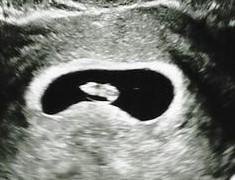

6 седмица